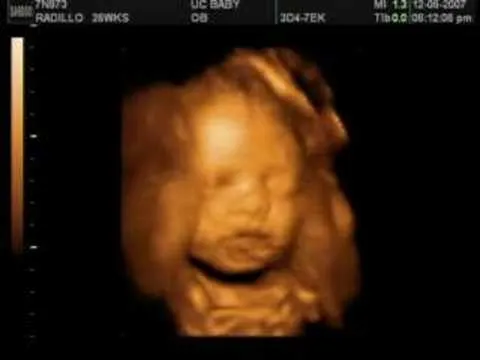

Ultrasonido en 4d a los 5 meses

Ultrasonido 3D/4D - Nathaniel (Parte 2) - YouTube